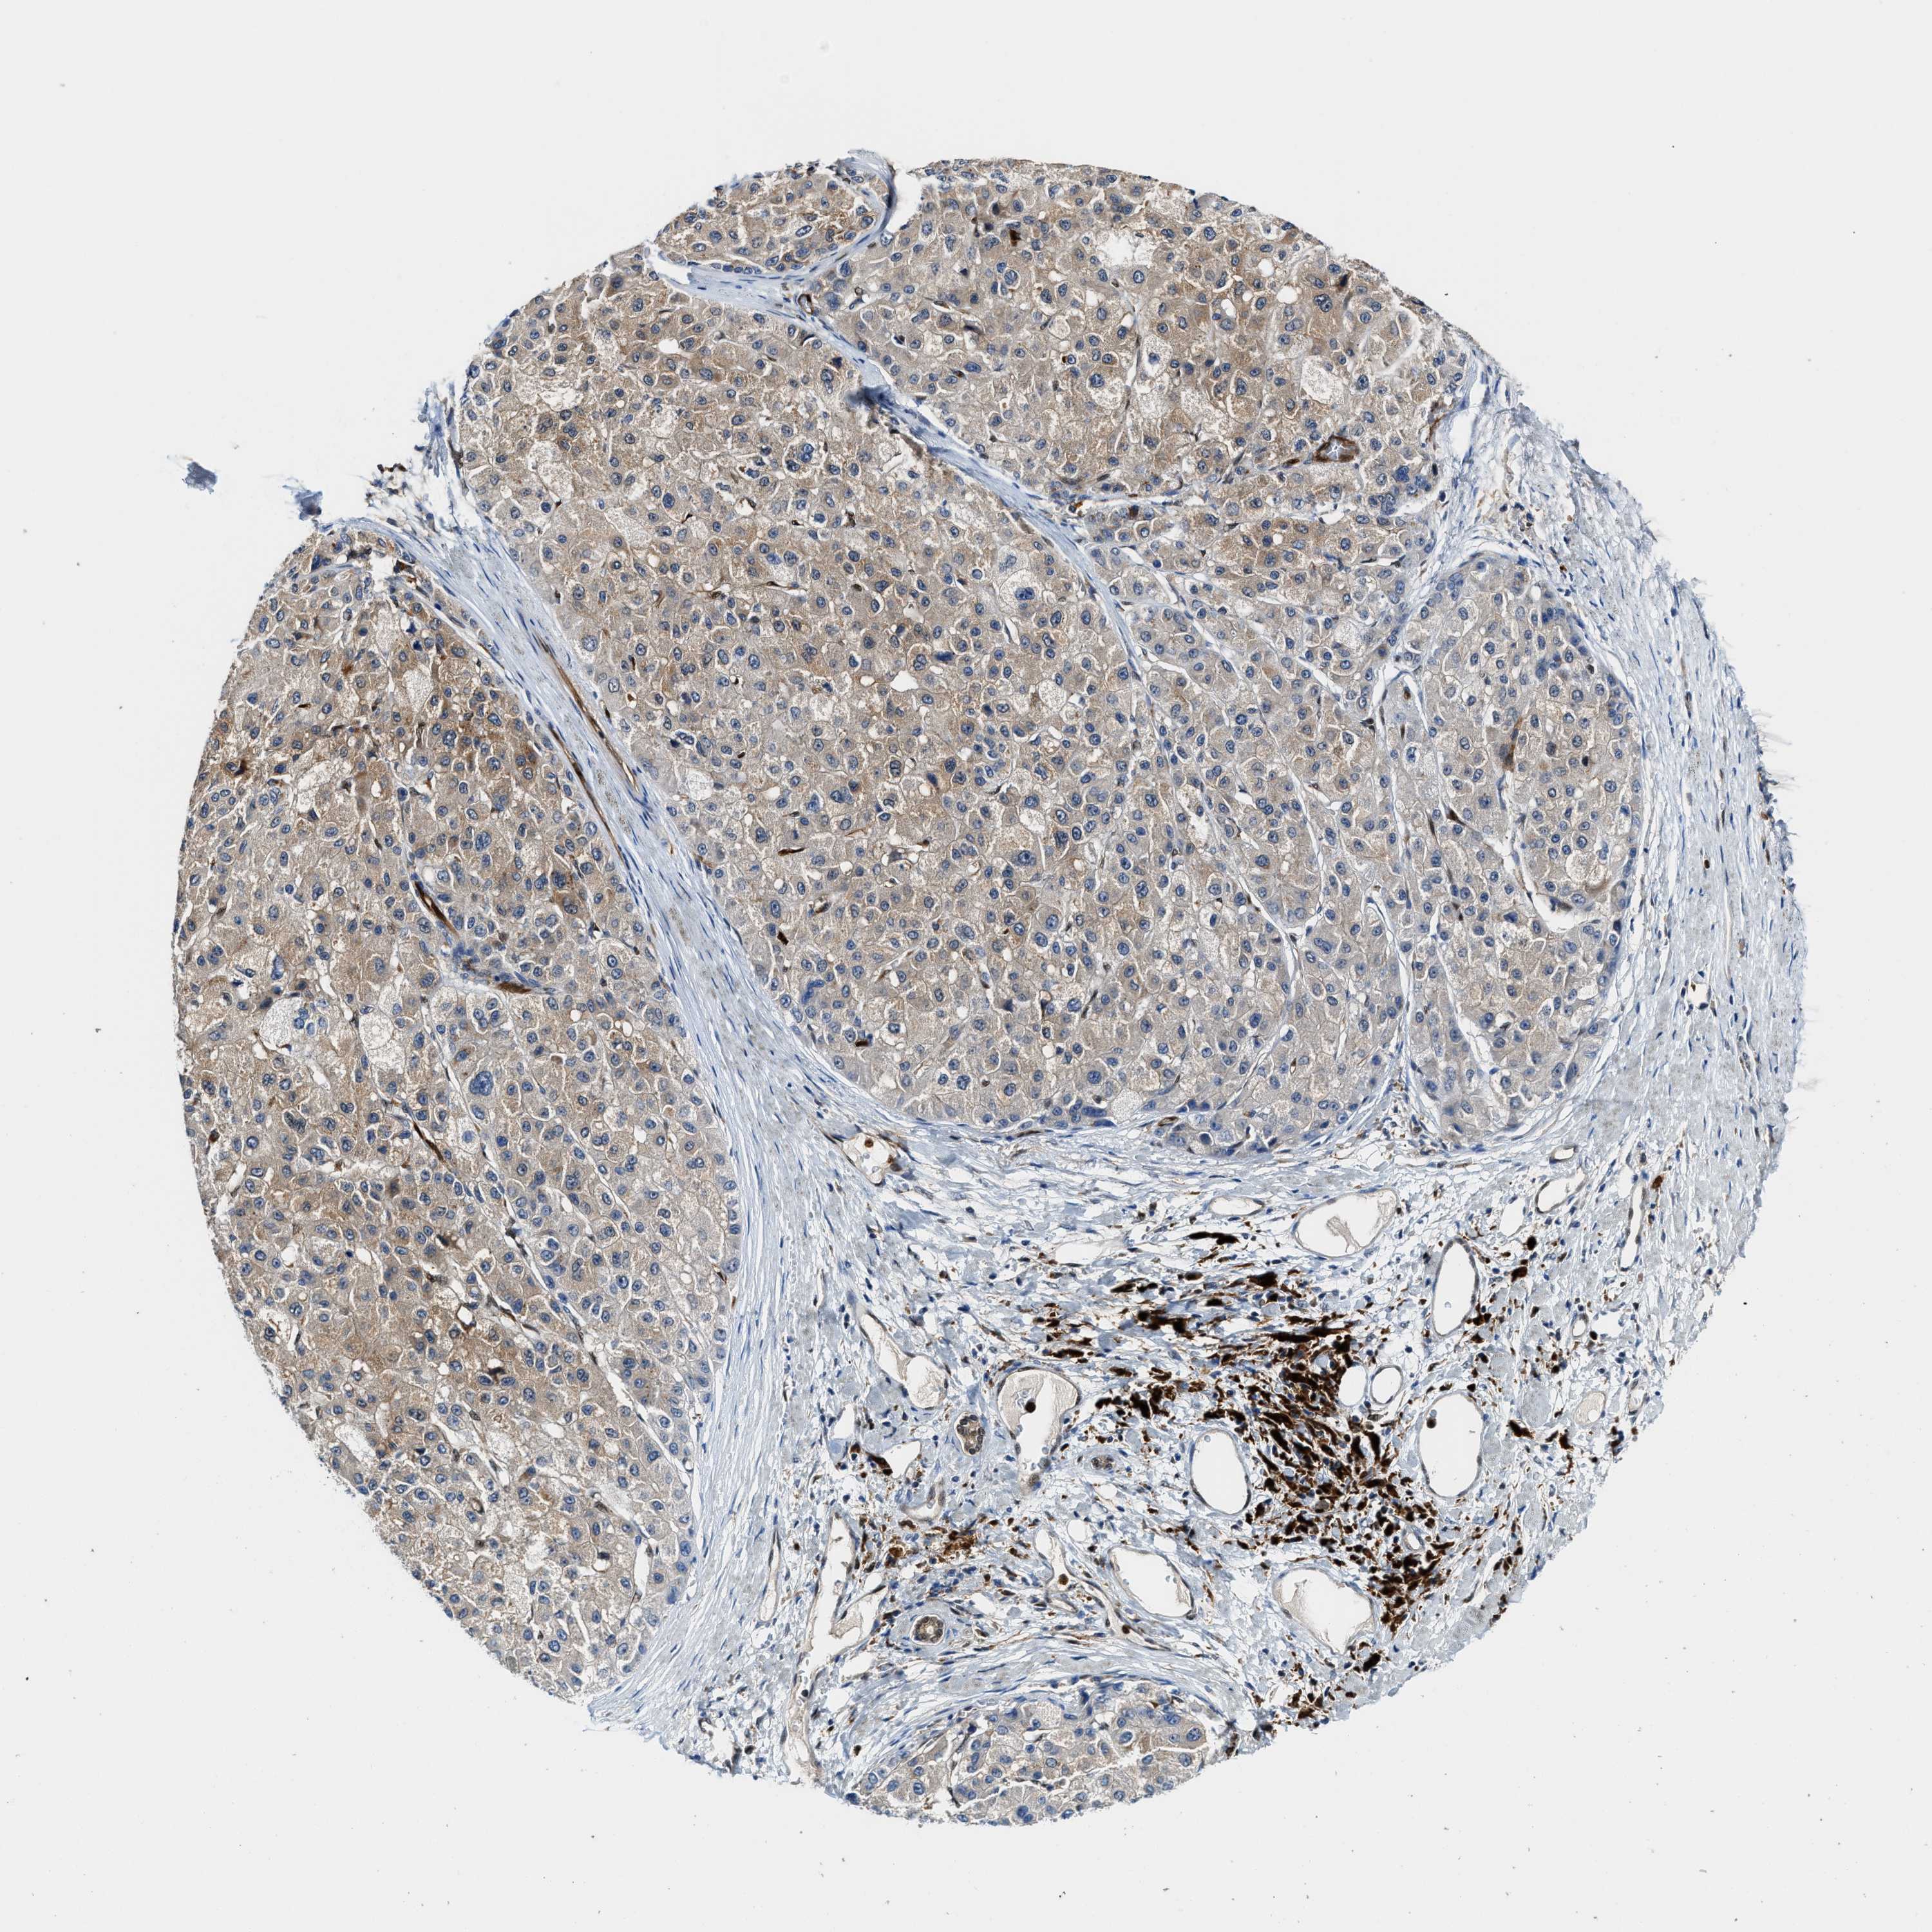

LIVER CANCER - Protein expressioni

A mouse-over function shows sample information and annotation data. Click on an image to view it in a full screen mode. Samples can be filtered based on level of antibody staining by selecting one or several of the following categories: high, medium, low and not detected. The assay and annotation is described here.

Note that samples used for immunohistochemistry by the Human Protein Atlas do not correspond to samples in the TCGA dataset.

Antibody stainingi

Antibody staining in the annotated cell types in the current human tissue is reported as not detected, low, medium, or high, based on conventional immunohistochemistry profiling in selected tissues. This score is based on the combination of the staining intensity and fraction of stained cells.

Each image is clickable and will lead to virtual microscopy that enables deeper exploration of all samples and also displays staining intensity scores, fraction scores and subcellular localization as well as patient and tissue information for each sample.

Antibody HPA008399

Antibody HPA017017

Antibody CAB015221

Staining

High

Medium

Low

Not detected

Intensity

Strong

Moderate

Weak

Negative

Quantity

>75%

75%-25%

<25%

None

Location

Nuclear

Cytoplasmic/membranous

Cytoplasmic/membranous,nuclear

Cholangiocarcinoma

Carcinoma, Hepatocellular, NOS